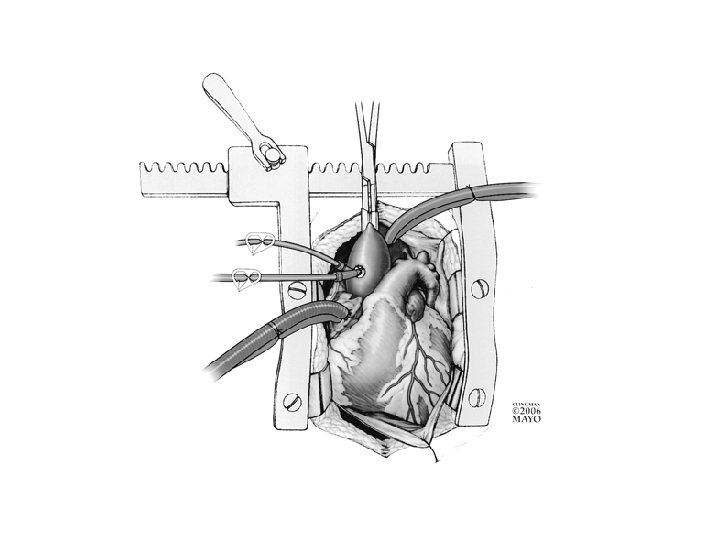

Коронарная хирургия без АИКа Преимущества ► Меньшая смертность и заболеваемость ► Отсутствие провоспалительного активирования Коронарная хирургия без АИКа Преимущества ► Меньшая смертность и заболеваемость ► Отсутствие провоспалительного активирования ► Меньше осложнений со стороны почек ► Лучшее течение после операции со стороны дыхательной системы ► Меньше неврологических осложнений ► Меньше необходимость гемотрансфузий ► Меньшая длительность лечения в стационаре ► Экономически выгоднее

Коронарная хирургия на бьющемся сердце Предполагаемые недостатки ► Ненадежность анастомоза ► Невозможность анастомозирования ► Коронарная хирургия на бьющемся сердце Предполагаемые недостатки ► Ненадежность анастомоза ► Невозможность анастомозирования ► Склонность к неполной реваскуляризации